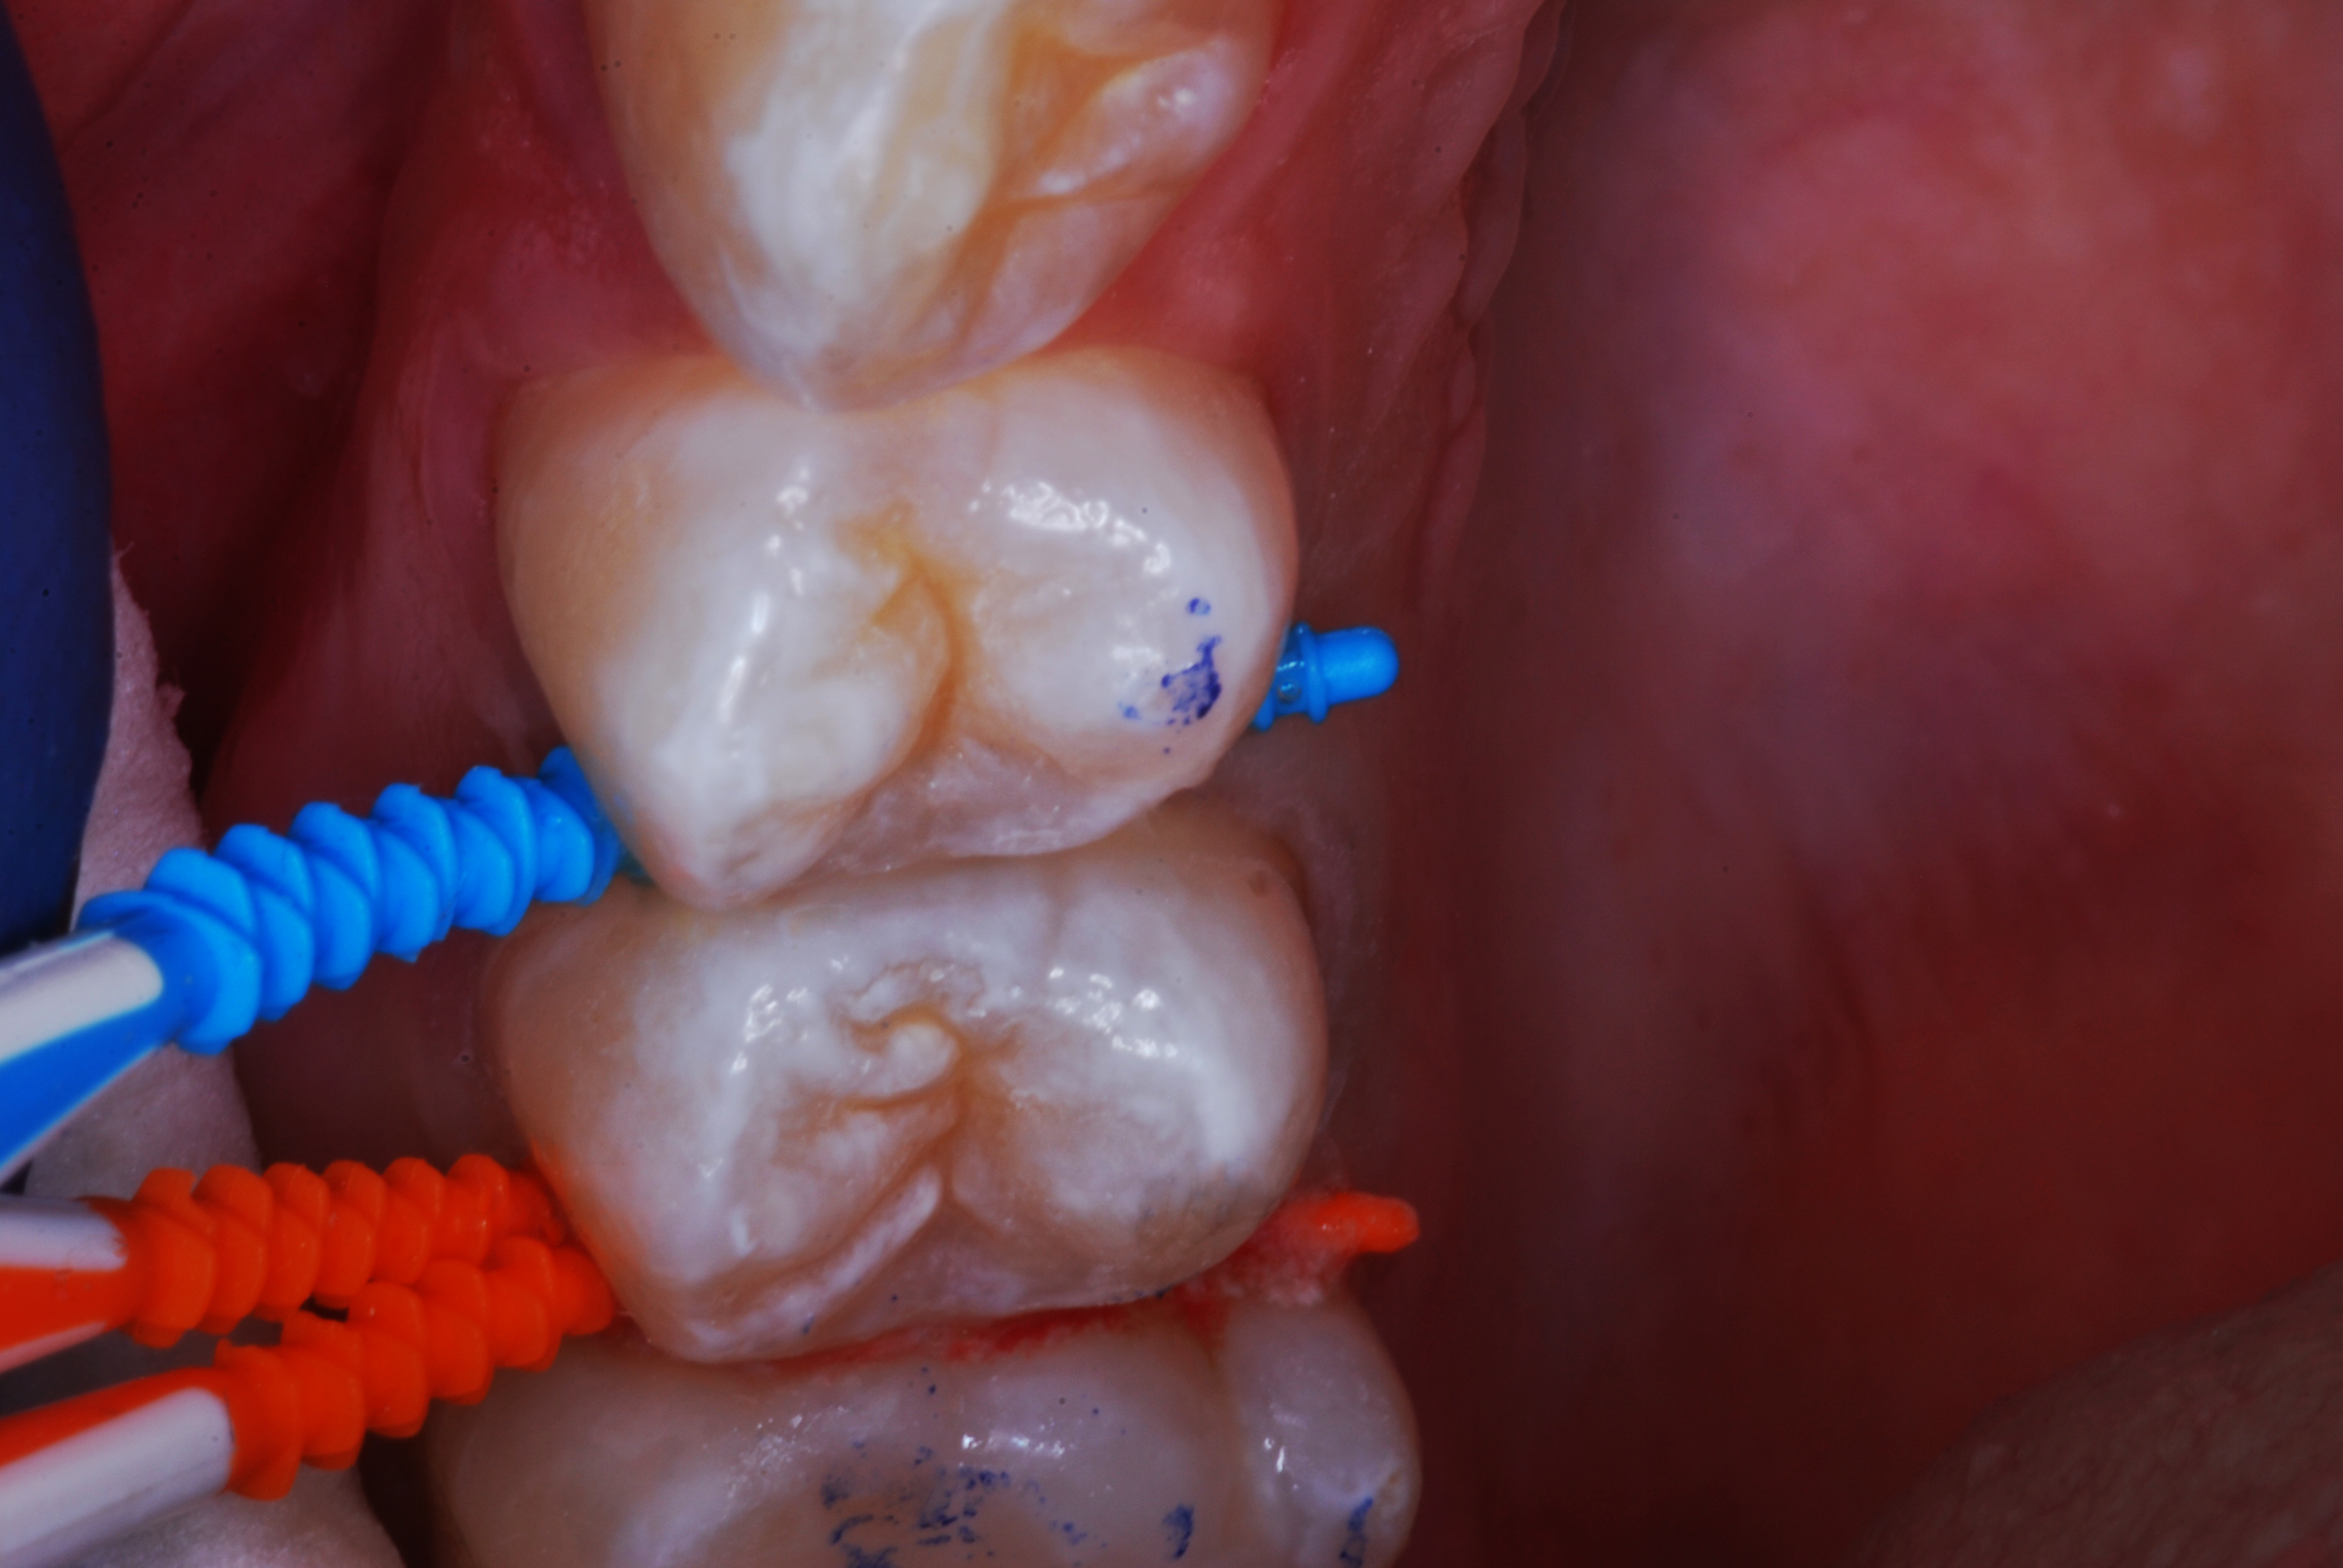

(20.) SDF proximal applications for small first and second molar caries lesions in teenage orthodontic patient, followed by preventive fluoride varnish cover of the area.

Figure 20

(21.) SDF proximal applications for small first and second molar caries lesions in teenage orthodontic patient, followed by preventive fluoride varnish cover of the area.

Figure 21